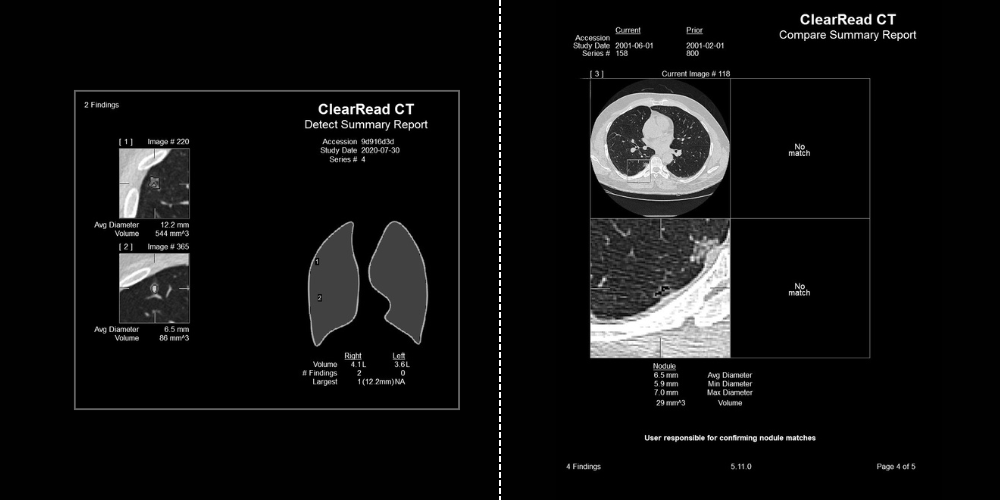

Pulmonary Nodules Automated nodule analysis, current and prior, and reporting to lighten cognitive load

- Fully-automatic nodule detection and analysis

- Quickly & easily compare nodule findings with prior exams – monitor changes in volume, diameter, and doubling time